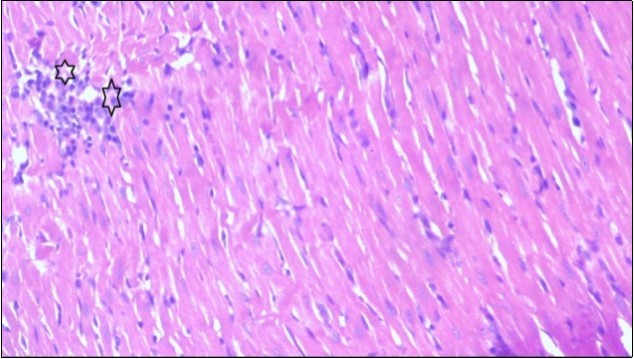

An important organ that is affected directly by the obesity which is the heart: The heart is the main important organ in circulatory system, the heart wall has three basic layers; the tunica intima of the heart is called endocardium, the tunica media of the heart is called the myocardium, the tunica adventitia of the heart the epicardium. The histological examination of the hearts of control rats feeding standard diet showing normal cardiac tissue with elongated, unbranched multinucleated muscle fibers (arrow), (Figure 1). The rats are feeding (HFD) for 2 weeks (obese rats) showing large number of inflammatory cells (star), degeneration muscles fiber ,circle and congested Blood vessels (arrow) (Figure 2). By comparison hearts of rats are treated by fennel after obesity and control rats observed show improved cardiac tissue with less infiltration (star) and well organized elongated muscle fibers with peripheral nuclei (arrow) (Figure 3). While examination of rats heart that treated by ator after obesity appears show less improved cardiac tissue with few inflammatory cells between disorganized muscle fiber (star), (Figure 4). While combined hearts of rats are treated by fennel and ator after obesity and control mice are showing nearly cardiac tissue with well-organized muscles fibers (arrow), (Figure 5).

Figure 2.Photomicrograph of heart section of an obese rat showing large number of inflammatory cells (star), degeneration muscles fiber, circle and congested Blood vessels (arrow), (H&E) (400X).

Photomicrograph of heart section of  an obese rat showing large number of inflammatory cells (star), degeneration               muscles fiber, circle and congested Blood vessels (arrow), (H&E) (400X).